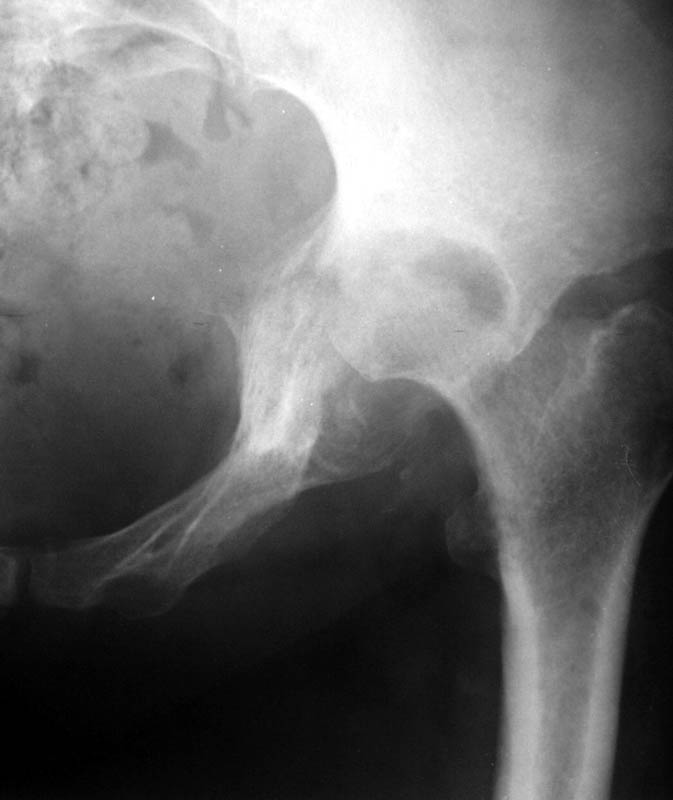

Женщина, 45 лет. В марте перенесла левосторонний коксит неизвестной этиологии. Специфику и онкологию исключили.

Интраартикулярных инъекций не было. Сейчас процесс клинически и рентгенологически - стабилизировался. Состояние вполне удовлетворительное. Предполагается тотальное эндопротезирование с пластикой полости аутокостью. Возможна ли бесцементная <чашка>? Заранее благодарю! С уважением, А.В.Владзимирский